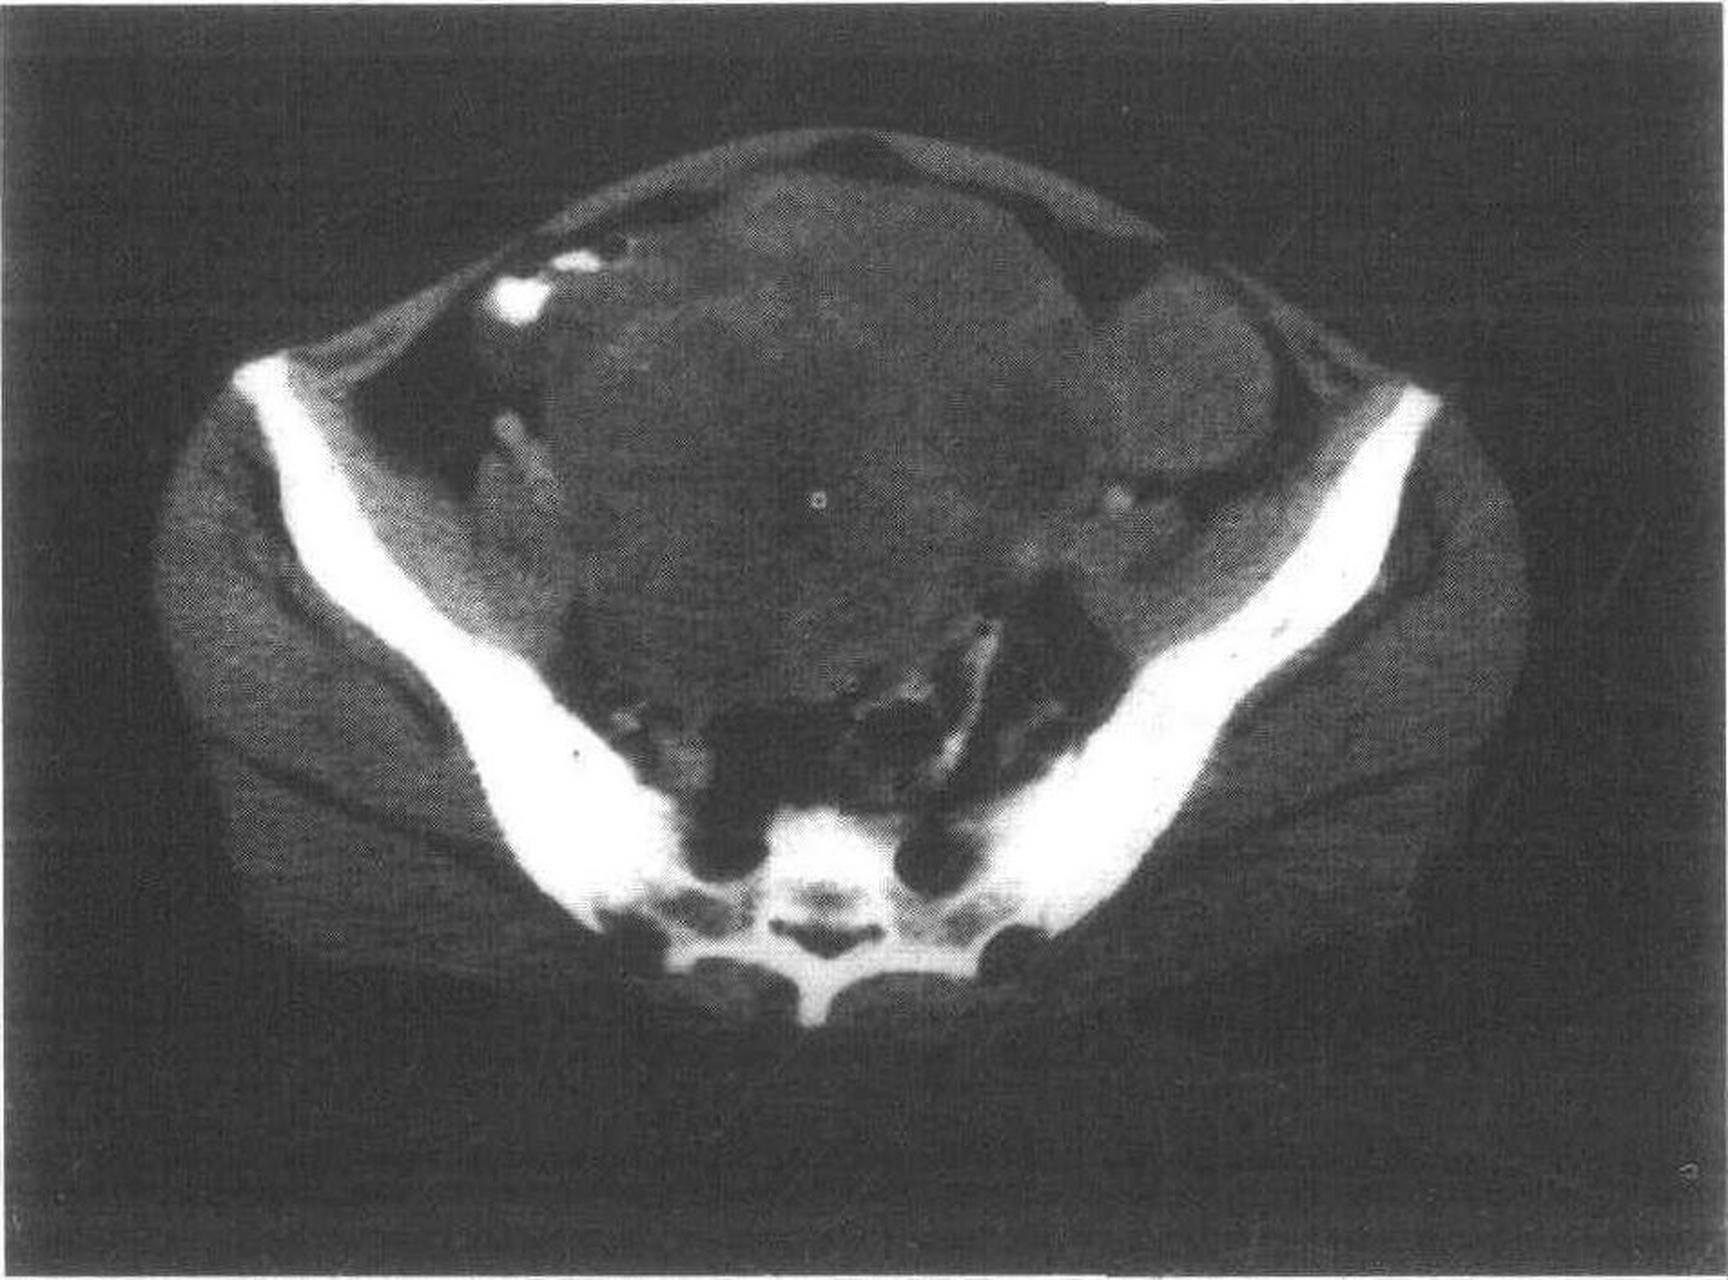

女,51岁,子宫内膜癌术后2年病史,1个月前出现右腰骶部疼痛,并向右下肢